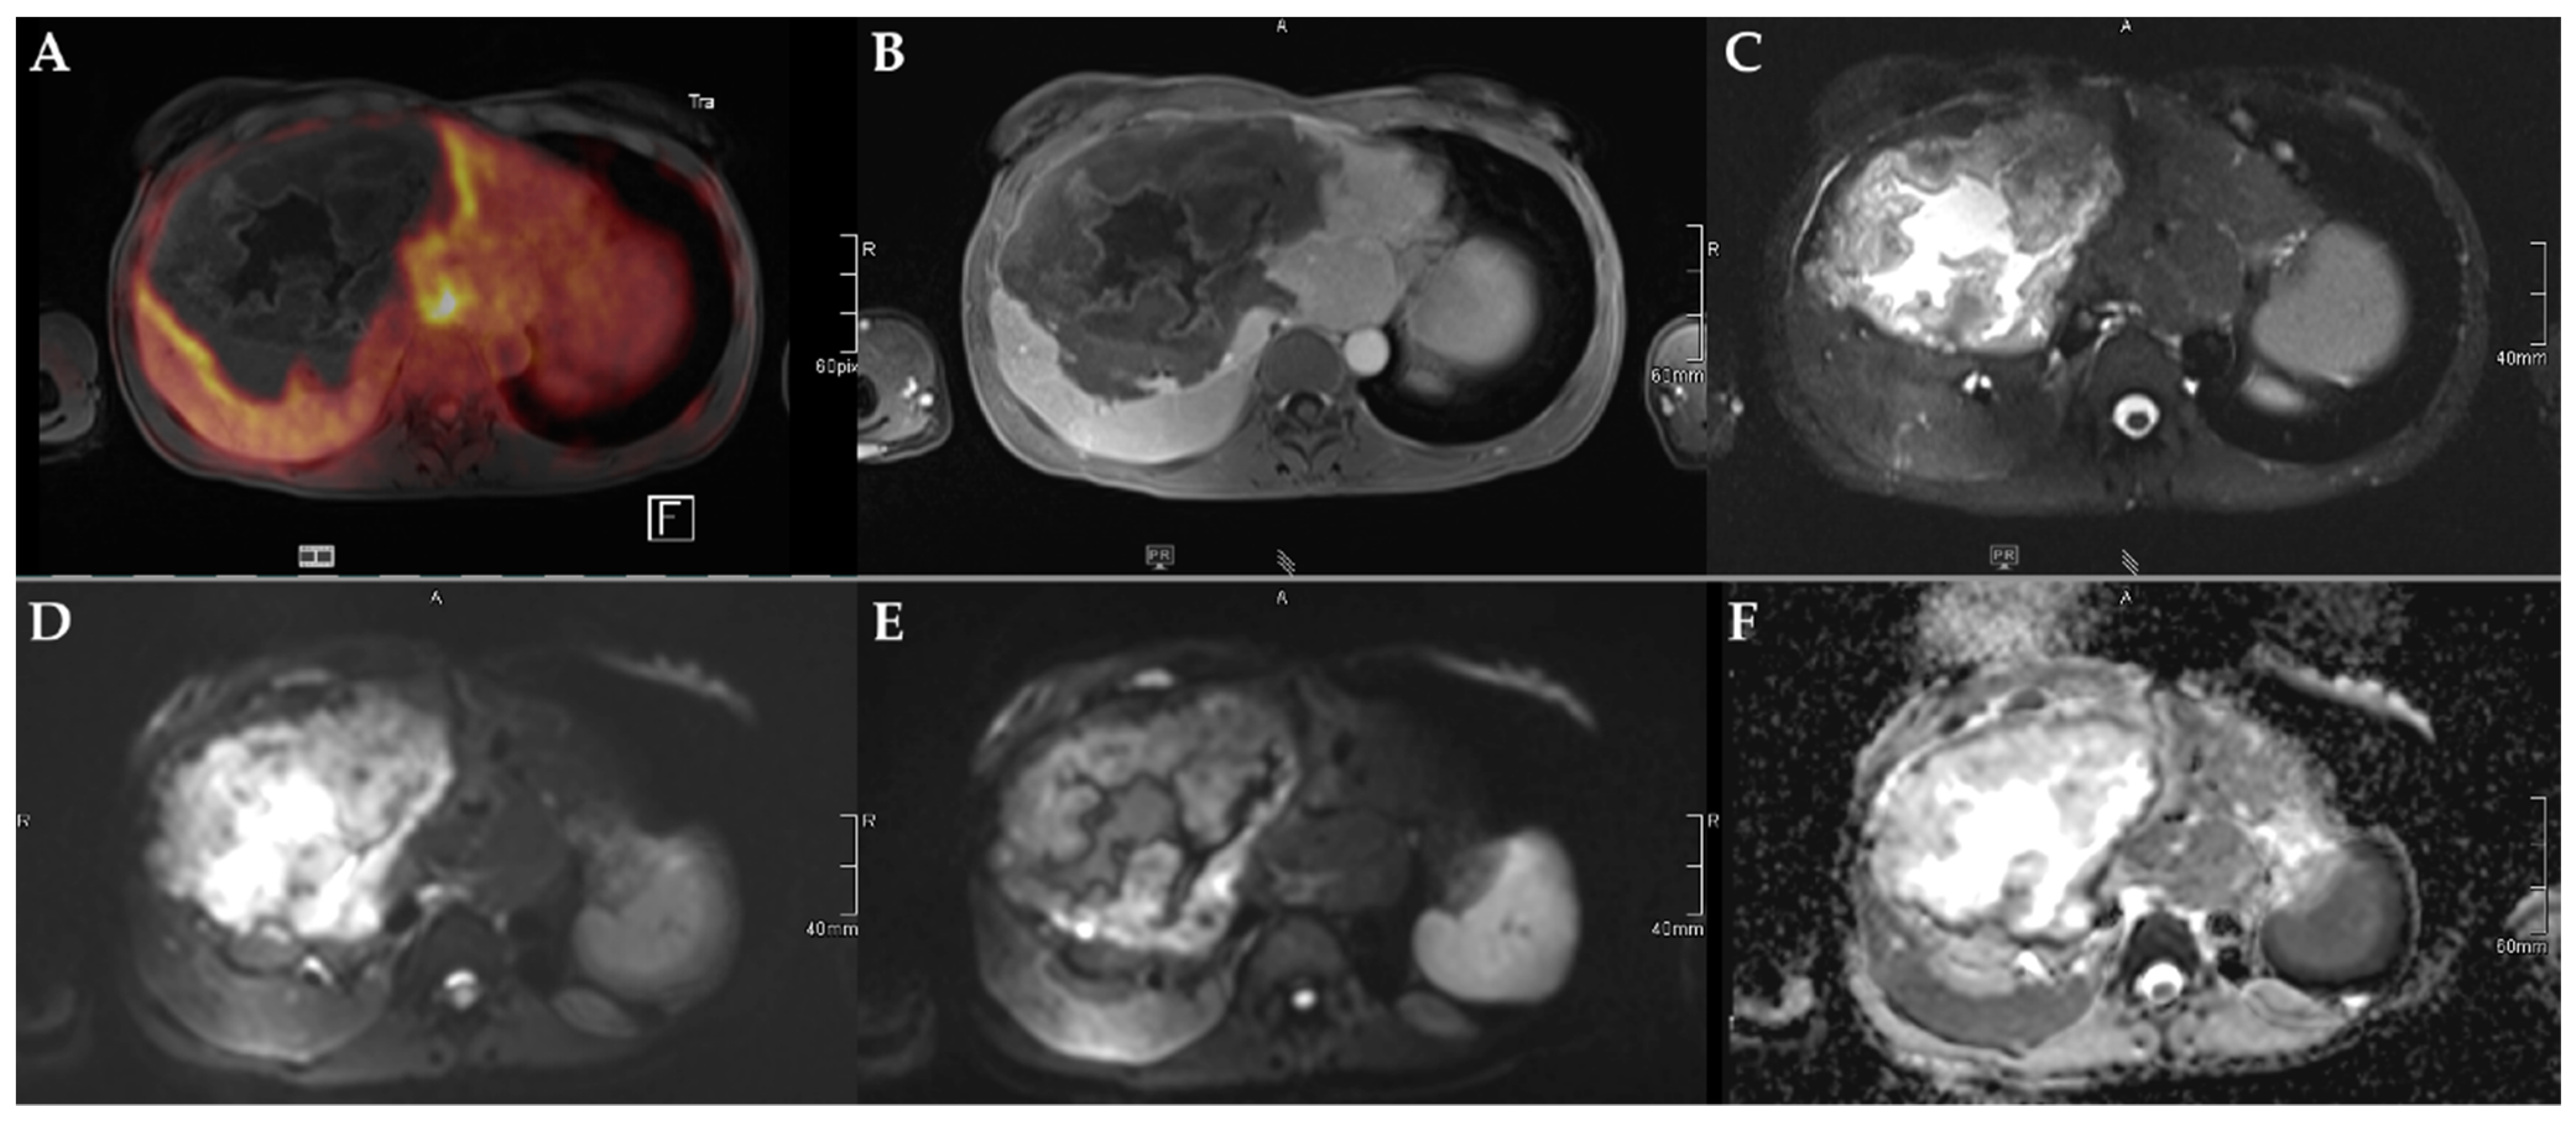

Figure 3.

45-year-old female patient with AE and involvement of liver segments IVa–VII and Kodama Type 3 lesion. Increased FDG uptake is observed at the lesion rim (A) with increased uptake of the contrast agent (B). High signal intensity is present in the central cystic parts in T2w imaging with fat suppression (C). Diffusion imaging demonstrates a high signal at a low b-value (b50) in the central parts of the lesion (D), a low signal at a high b-value (b800) (E), and high ADC values (F), indicative of no diffusion restriction.